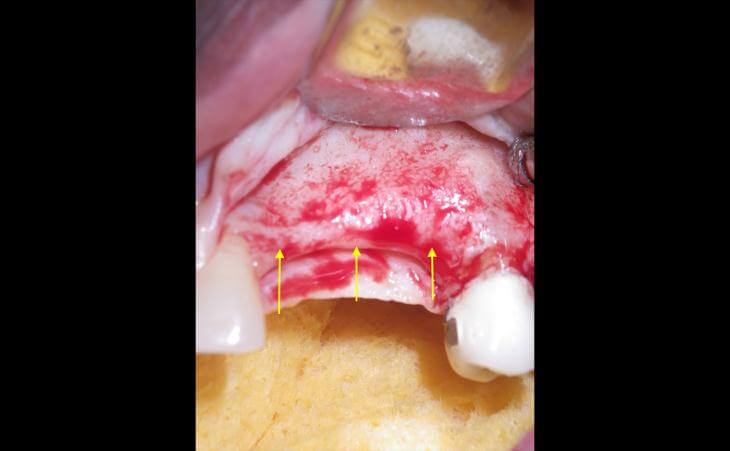

Pre surgical ct scan showed severely resorbed jaw bone After 4 months - a CT scan shows amazing bone volume regenerated

After 4 months - a CT scan shows amazing bone volume regenerated  Newly grown bone on CT scan

Newly grown bone on CT scan